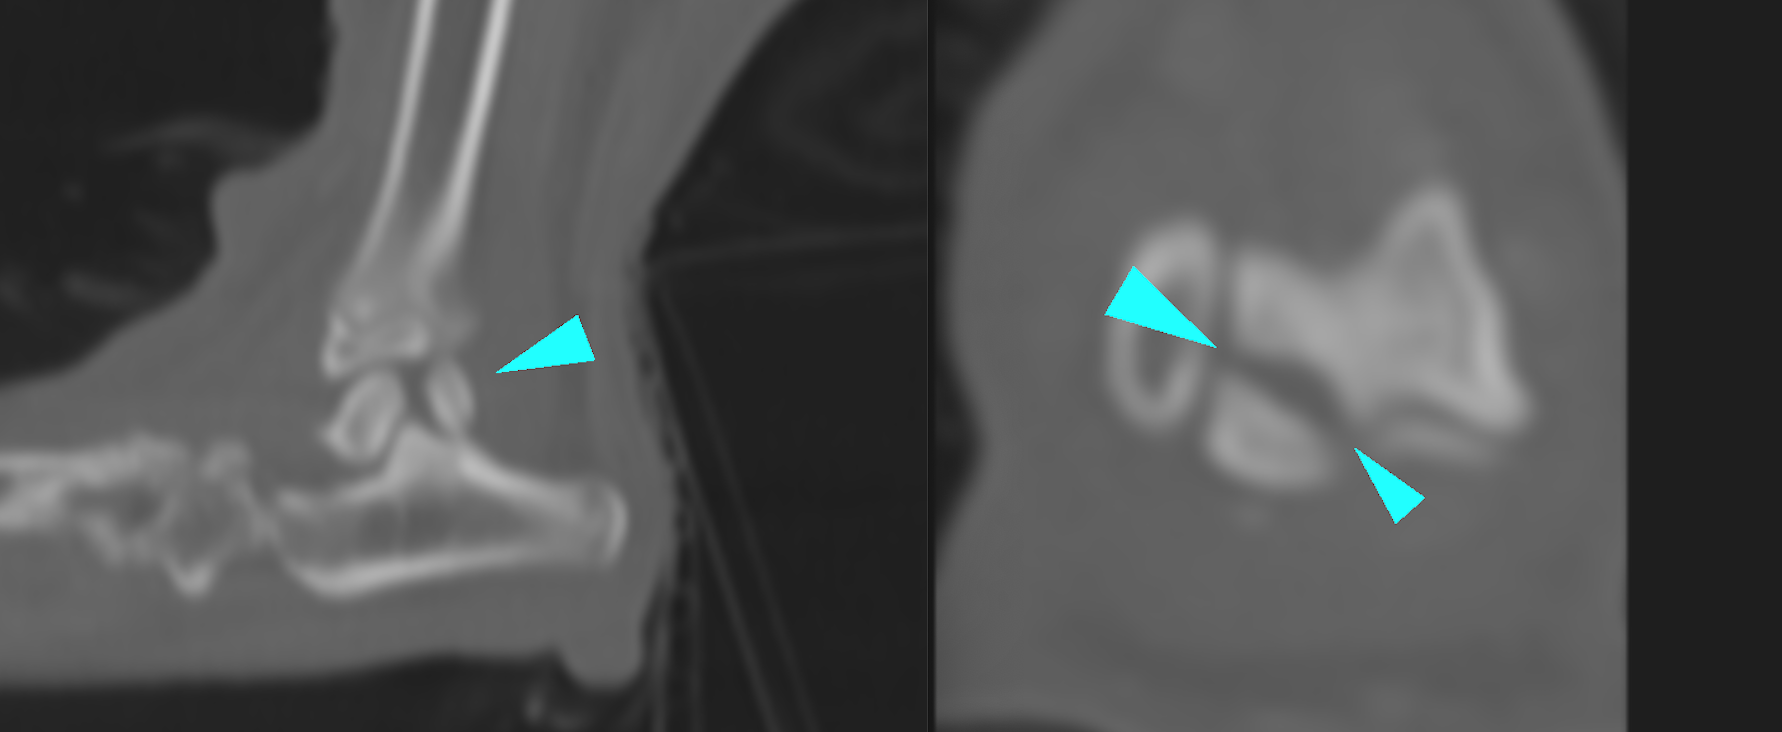

整形外科の雑誌であるVeterinary and Comparative Orthopaedics and Traumatologyに磯野の論文である「Tibial Torsion Malalignment in Small Dogs with Medial Patellar Luxation」が掲載されました。パテラ内方脱臼に対し、脛骨粗面と足根骨の捩れが関与しているをことを示し、その指標の一つを提言した内容になります。ご興味ある方はご覧ください。